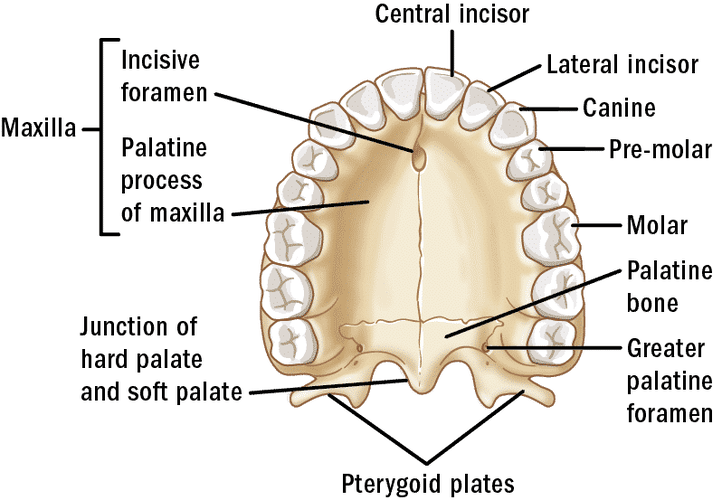

Y'all know that the palate has a big influence in the maxillary and so in the attractiveness, so i was thinking;

The tongue is the natural expander of the palate, during swallowing we apply pressure on the palate with the tongue, and also while eating we store food in our cheeks while we chew using the outer edge of our molars and rest of teeths, so i got a question:

What if we chew using the inner edge of our teeths and applying constant pressure on the food and palate with our tongue?

If we do that would acelerate the process of expansión in our palate?